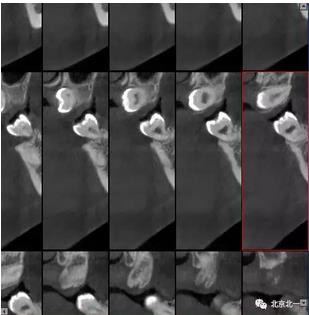

圖三:橫斷面可見智齒水平橫向腭側(cè)。完全骨埋伏。

360截圖20170124104308406.jpg

圖四:冠狀面截圖牙根位于唇側(cè),牙冠位于腭側(cè)。

360截圖20170124104319726.jpg

圖五:矢狀位截圖可見牙冠截面。

360截圖20170124104334678.jpg